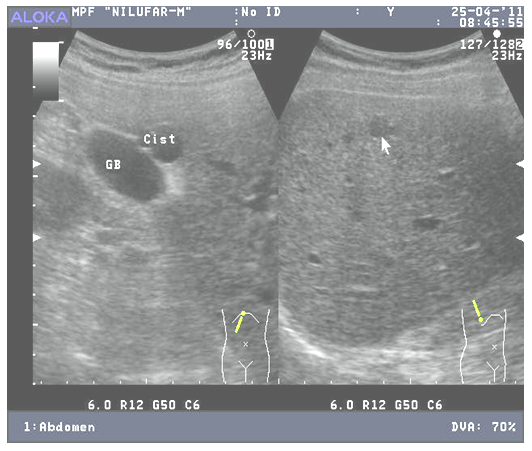

When conducting ultrasound monitoring of the condition of the residual cavity (RC) after echinococcectomy (EE) of the liver, our goal was to study the dynamics of the processes occurring in the RC after various types of operations and compare the results obtained with the methods of surgical correction. Also of scientific and practical interest is the establishment of a correlation between the clinical manifestations of RC suppuration and ultrasound data, which will allow timely therapeutic measures to be taken without bringing the process to true suppuration.21 (9.7%) patients were under observation for complicated RC after liver EE, of which 18 (14.5%) were in the comparison group, 3 (3.2%) were in the main group. The frequency of RC suppurations from the total number of patients with RC complications was 3.7% (8 patients), the presence of fluid was 5.9% (3 patients). Moreover, in the comparison group, complications of RC in the form of suppuration amounted to 6.4% (8 patients); in the main group, RC suppuration was not observed in any case. Fluid accumulation was 8.1% (10 patients) and 3.2% (3 patients). From the analysis of medical records in the comparison group, 16 (12.9%) patients with complicated residual surgery for LE were completed with external drainage of the cyst cavity, only in 2 (1.6%) the operation was completed with closed EE. In the main group, 3 (3.2%) patients with complicated RC were operated on using a combined EE method with drainage using one drainage tube.In the comparison group, 2 patients began to experience small RCs up to 1.5 cm in diameter on the 4th day. On the 5th day, the sizes of the cavities reached 3.5 and 5 cm in diameter, respectively, with liquid heterogeneous contents. In the long-term period, during dynamic ultrasound, fluid accumulation in the RC (2.5 cm) was observed at 5 months after surgery, in which no pathological accumulations in the RC were observed during ultrasound on the 2nd and 3rd days. At the 6th month, the diameter of the formation increased to 4.5 cm.We see that dynamic correction of drainages located in the RC is the most important method of preventive treatment and prophylactic measures in diagnosing signs of RC formation and infection. Our experience has shown that drains with a diameter of less than 1 cm were often used, which did not provide sufficient outflow of contents. In addition, with a reduction in the volume of RC, as well as with abdominal excursion, mixing of drainages is often observed. In this regard, we fixed the drainage with catgut thread by stitching one of its edges to the bottom of the cavity. Catgut is used 2/0 - 3/0. A drain with an internal diameter of at least 1 cm has 3-4 side holes. Next, we fix it at the outer edge of the fibrous capsule and stitch it to the skin of the anterior abdominal wall.By the time the drainage is removed on days 5-6, the catgut relaxes and the drainage is evacuated without any difficulty. In a similar way, we have already fixed drains in patients of the main group. Only 1 (1.1%) of them had mixed drains and prolapsed. Patients with RC after liver EE were characterized by a polymorphism of clinical manifestations - from a latent and asymptomatic course to the appearance of hepatomegaly. The absence of any clinical symptoms occurred in 5 (11.6%) patients; in the rest, pain, a feeling of heaviness in the upper abdomen or discomfort after eating were common. The nature of the pain and its localization depended on the size of the RC and concomitant lesions of the hepatopancreatoduodenal zone. Thus, in patients with small cavity sizes, the pain was periodic, moderately aching and localized equally often both in the right hypochondrium and in the epigastric region; in patients with large RC, the pain was constant, dull and localized mainly in the liver and right hypochondrium.The second characteristic symptom of RC after pain after EE of the liver is more or less pronounced hyperthermia with signs of intoxication of the body.Diagnosis of RC complications after liver EE included: detection of RC and its differentiation; establishing its size, prevalence and segmental localization; establishing a connection between the RC and the intrahepatic bile ducts; assessment of the nature of the content of the RC; choosing a treatment method or eliminating the need for it. After EE, dynamic ultrasound is performed from the next day. The liver was examined in both transverse, oblique, and direct directions. To capture the image, if necessary, a Polaroid photo attachment was used.Adhering to this tactic, it was possible to identify a number of characteristic sonographic signs complicated by RC and their relationship with clinical symptoms. During dynamic ultrasound of operated patients, a cavity with fluid accumulation was identified. Differential diagnosis from hydatid cysts was characterized by the presence of a double contour of liver formation. This sign in 100% of cases indicates the parasitic nature of the cyst.RC was characterized by uneven contours that had scalloped or folded outlines. At the same time, the ultrasound picture of RC and parasitic cyst differed significantly: for example, in the presence of EC disease, a smooth contour, a thin capsule and liquid, round formations inside the cavity were significantly more often detected. In the presence of RC, an uneven contour of the lesion and echogenic consolidation of pericystic tissue were more often observed (Fig. 1).  | Figure 1. Patient M. History No. 624/252. On the projection of the 7th segment, 10 x 10 x 12 mm, irregular oval shape, smooth, clear contours, have a thin capsule of 1 mm, contain liquid, the formation is in contact with the body of the gallbladder |

The shape of RC gradually approached slit-like or triangular, in contrast to the round configuration characteristic of EC.In doubtful cases, dynamic monitoring was continued. The dynamics of the size and localization of the formation allowed us to draw a final conclusion about its nature. During dynamic ultrasound, the size of liver RC varied from 15 to 100 mm or more, but most often residual cavities were diagnosed from 20 to 60 mm in diameter - 26 patients or 60.5%.Diagnosis of RC in these patients was also based on fistulography data in 4. This tactic allowed us to minimize the number of postoperative complications from RC.We operated on 79 (63.7%) patients for uncomplicated hydatid LE and 48 (51.6) patients in whom RC formation and infection occurred in the postoperative period.In 8 cases, semi-closed versions of EE were performed, and only in one observation was closed EE performed. The open version of the operation is usually performed forcedly.Closed EE was performed in 1 patient, who underwent closed EE; the cyst was located in the 4th segment. Its diameter was 8 cm.On the 5th day, in the evenings the temperature began to rise to 37.5 - 38°C. Ultrasound data already on the 2nd day revealed the presence of RC up to 2 cm in diameter. On days 4-5, the RC began to have clearer contours. In its cavity, fluid was clearly visible.We observed fluid accumulation in the RC after semi-closed EE by tamponade of the fibrous cavity with a strand of omentum. In addition to filling the fibrous cavity with an omentum, a vinyl chloride drainage was introduced into it, which was installed to the bottom of the cavity and fixed to the fibrous capsule and to the skin of the patient’s anterior abdominal wall. Only on the 6th - 7th day small cavity formations (1.5 - 2 cm) began to be visualized. On the 9th day, the sizes of the cavities reached 3.5 and 5 cm, respectively. The same period also coincided with the appearance of insignificant, up to 3.5 ml, discharge from the drainage, which was cloudy and odorless.In order to study its nature, bacteriological studies were carried out. As a result of the latter, the following strains of bacteria were identified: Escherichia coli. Staphylococcus aureus. Clinical signs of the formation and infection of residual cavities first appeared with a typical clinical picture only on the 11th - 12th day after the operation. A semi-closed EE was performed by suturing the fibrous cavity from the inside. The first three days of the early postoperative period were unremarkable. On the 4th day, it was discovered that the drainage did not reach the bottom of the sutured cavity by about 3 cm and there was a level of turbid liquid at the bottom. Having cut off the skin thread fixing it, the drainage was moved to the bottom of the wound, re-fixed and active aspiration of the contents was established.Thus, after EE from the liver for hydatid echinococcosis, dynamic ultrasound allows us to timely identify early signs of the formation and infection of RC, as well as carry out the necessary therapeutic measures. At the same time, sonographic signs of RC suppuration precede the appearance of clinical manifestations by an average of 4-5 days.Those operated on for hydatid LE complicated by suppuration were 23 (18.6%) and 21 (22.5%), respectively. In 3 cases, with suppurating ECs and their localization in 6-7 segments of the liver, open ECs were performed, leaving two drains in the cavity. 6 have semi-closed EEs with one drainage left in the RC. In 3 of them, according to ultrasound data, signs of inadequate drainage appeared already on the 2nd - 3rd day after surgery. Dynamic sonographic observation revealed that from the 3rd to 4th day after surgery, non-drainable fluid remained at the bottom of the cavity, where the cause in 2 patients was biliary fistulas. The priority of ultrasound in detecting infection and suppuration of RC was not as obvious as in the previous group. According to ultrasound data, on the 4th - 6th day after surgery, a stable level of fluid appeared at the bottom of the RC and a non-functioning drainage occurred.The open version of EE was used in only 3 patients. This is due to the absence of a sufficiently pronounced omentum and the fact that the screwing in of the edges of the fibrous capsule deformed the lobar bile ducts, which was diagnosed by intraoperative cholangiography.In 17 (13.7%) patients in the comparison group, the failure of the measures taken was an indication for relaparotomy and drainage of cavities. Only 1 (0.8%) of them underwent PAIR-PD. In the main group, laparoscopic RC sanitation and drainage were performed in 3 (3.2%) cases, and PAIR-PD in 3 (3.2%) cases.Treatment of complications of residual cavity. The main cause of specific complications after traditional methods of EE (combined and open) was the leaving of a dense, calcified fibrous capsule, bearing bile fistulas in its thickness. RC in the presence of such a fibrous capsule cannot be reduced. With closed EE, the applied sutures, as a rule, erupted and formed cavities where bile accumulated from the puncture sites, which contributed to the formation of cystobiliary fistulas, beats and their subsequent suppuration.With a dead parasite and complicated echinococcosis, due to the destruction of the cuticular membrane and partially fibrous capsule, conditions were created for the pathogen to penetrate beyond the hydatid into the tissue of the host organ. Under these conditions, traditional EE methods, even with removal of the fibrous capsule, did not provide radical treatment in all cases. Thus, a significant number of postoperative purulent-inflammatory complications from RC after traditional EE methods dictated the need to expand the indications for minimally invasive interventions.Endovideosurgical interventions allow us to consider it a promising direction in surgery for echinococcosis, but not as an alternative to traditional ones. Transfistula endovideoscopy of the RC liver was used in the treatment of 3 patients with functioning drainage of the RC liver due to the formation of external purulent-biliary fistulas, where in this case coagulation of the cystobiliary fistula was performed.All 38 patients underwent puncture treatment. The indication was the presence of signs of the presence of infected liquid contents during dynamic ultrasound and the addition of the clinical picture of RC suppuration. An RC diameter of up to 7 cm was noted in 1 patient, a dense mass measuring 4-7 cm in 2 patients, and a homogeneous formation up to 5 cm in 4 patients. For RC with a diameter of more than 40 mm, we performed puncture and drainage treatment under ultrasound control. It included the following: choosing the trajectory for advancing the puncture needle; inserting a puncture needle into the cavity formation; passing the conductor into the cavity formation; inserting a drainage tube (catheter) into the cavity; aspiration of the contents of cavity formation, medicinal effects, sclerotherapy; removing the drainage tube (catheter).The puncture-drainage method was carried out in an operating room equipped with Aloka SSD 260 ultrasound equipment and an X-ray television installation from FISCHER IMAGING corporation (Germany).Methodology: The procedure was performed under local anesthesia after premedication with non-narcotic analgesics. Indications for puncture treatment were signs of intoxication, hyperthermia and the presence of a liquid formation more than 35 mm in diameter.When performing RC puncture, while passing the needle through the tissue, we controlled the trajectory of the needle tip along the dotted line on the monitor screen by turning on the Puncture function.The location of the puncture was determined individually. However, when hydatid echinococcosis is localized in the right lobe of the liver, the most common place is the 7-8 intercostal space along the axillary midclavicular line, and when localized in the left lobe, the area is approximately 3 cm below the edge of the xiphoid process. Then, under dynamic ultrasound control, puncture is performed with a No. 18 Chiba needle. Under the control of an X-ray machine, contrast is injected through a puncture needle, which makes it possible to clarify the size, shape and internal structure of the hydatid cyst. A guidewire is inserted into the RC through the lumen of the needle, followed by its expansion with dilators No. 9 and then No. 10. After removal of dilator No. 9, a pig-teil drainage tube No. 16F is installed along the internal lumen of dilator No. 10 in the RC. After dilatation, the dilator is removed and the drainage tube is fixed to the skin. The entire procedure is carried out under dynamic ultrasound and under the control of an X-ray television installation (Fig. 2). | Figure 2. I/B No. 2571/564. Ultrasound and X-ray television monitoring |